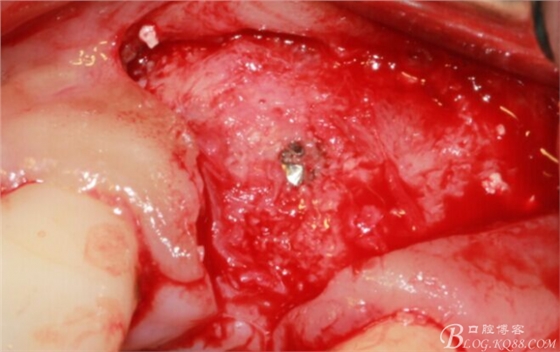

于是我果斷告知患者,手術(shù)失敗了,不能拖延,如不及時(shí)處理,炎癥繼續(xù)發(fā)展會(huì)很快波及鄰牙牙槽骨。患者接受我的建議。切開翻瓣,骨粉及生物膜消失了,骨吸收嚴(yán)重,幸運(yùn)的是,因?yàn)樘幚砑皶r(shí),鄰牙骨支持依然存在。

徹底掻刮。

有老師問我,為什么不在此時(shí)同期植骨同期植入植體?我的觀點(diǎn)是:不要一次做太多事情,做得越多風(fēng)險(xiǎn)越高。再說,此時(shí)軟組織不健康,沒有健康的軟組織如何能保證GBR的成功?所以,我僅放了一塊膠原蛋白就縫上了。